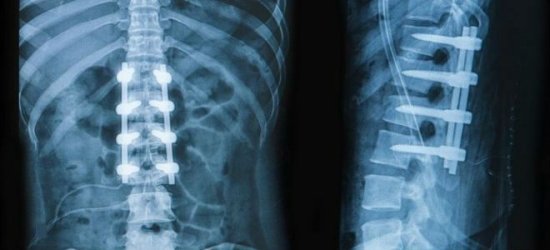

В результате переломов позвонков и других серьёзных травм позвоночного столба, спина внизу поясницы начинает усиленно болеть из-за того, что скелет ослаблен после травмы.

При переломе позвонков может наблюдаться сильнейшая боль в спине в целом, при локализации в левую или в правую части спины, или в конечности конечности. Если даже слабо надавить на позвоночник, то болевые ощущения серьёзно усилятся.

Типичные симптомы перелома позвонков:

- ограничение подвижности тела;

- снижение чувствительности, онемение рук и ног;

- мгновенное усиление болей при малейшем воздействии на позвонки;

- появление сильной утомляемости;

- появление одышки.

После обращения к травматологу потребуются лабораторные и аппаратные исследования, включающие в себя: анализ мочи и крови, рентгенографию, МРТ, электрокардиограмму . При лечении применяются как классические методы (фиксация и восстановление повреждённого позвонка), так и хирургические.

В качестве последствий травмы необходимо отметить запрет на тяжёлые физические нагрузки, обязательные профилактические осмотры у травматолога, проведение рентгенов. Запрет на физические нагрузки особенно важен, так как в ходе развития проблемы могут возникнуть осложнения, и боль из спинно-поясничной области может передаться в конечности.